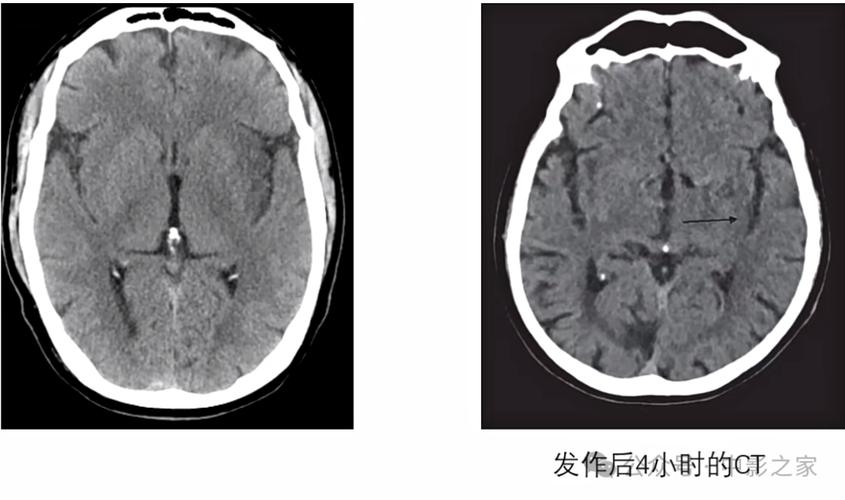

- 病灶小: CT上显示的梗塞范围很小,可能只是一个小点。